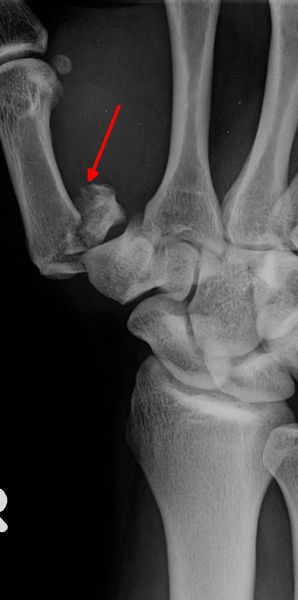

Bennettfraktur: basisnahe Schrägfraktur mit Gelenkbeteiligung, das Metacarpale I wird durch Sehnenzug bei dieser Bruchform immer verschoben werden.